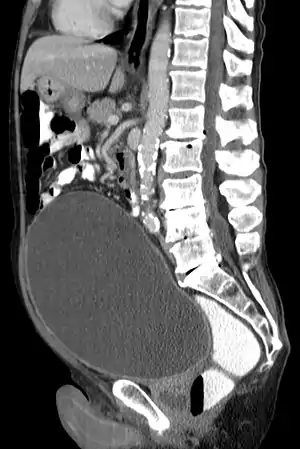

| Urinary retention with greatly enlarged bladder as seen by CT scan. | |